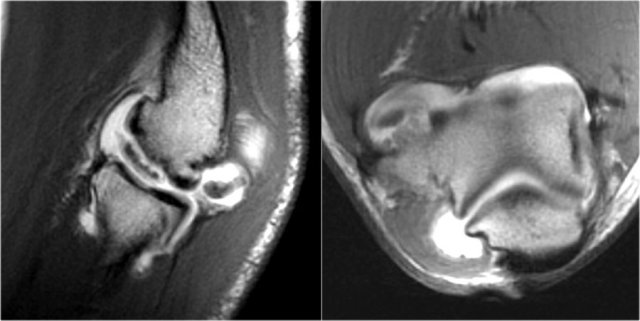

These images are of a 23 year old male who fell onto his outstretched hand two weeks ago while skateboarding.

On physical exam there was decreased range of motion of the elbow and tenderness along the lateral aspect.

First study the images, then continue reading...

What is the structure on the axial image behind the radial head?

Sagittal view:

• Again the characteristic pattern of marrow edema that is seen in posterior elbow dislocation with contusion in the anterior side of the radial head (red arrow) and on the posterior side of the capitellum.

• The radial head must have hit the posterior part of the capitellum.

The structure behind the radial head is the annular ligament.

It is irregular and thickened as a result of the posterior dislocation.